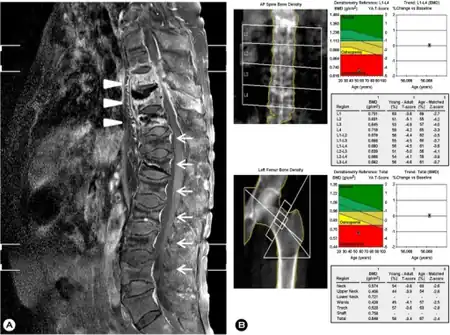

a) MRI of spine - spondylitis of T8, 9, 10 and subligamentous abscesses arrow b) Low bone mineral density at lumbar spine/femur | |